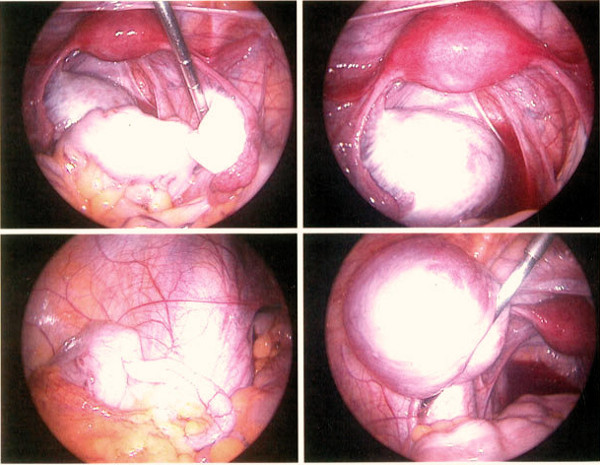

Гистероскопия

Носит наиболее высокую информативность.

Признаки вариабельны и зависят на указанной стадии от его формы.

На второй стадии отмечают неровность рельефа матки, вид напоминает разволокнённую мышечную ткань, визуализируют эндометриоидные ходы.

Полость органа плохо растягивается.